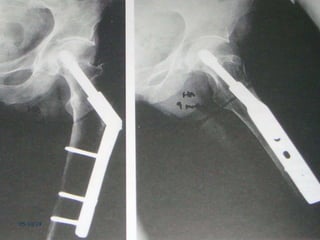

Tratamento cirúrgico

 Melhor método para o tratamento da

maioria das fraturas

transtrocantéricas: (Rockwood e

Sizínio)

 DHS

Tratamento cirúrgico  Melhormétodo para o tratamento da maioria das fraturas transtrocantéricas: (Rockwood e Sizínio)  DHS 05/10/19